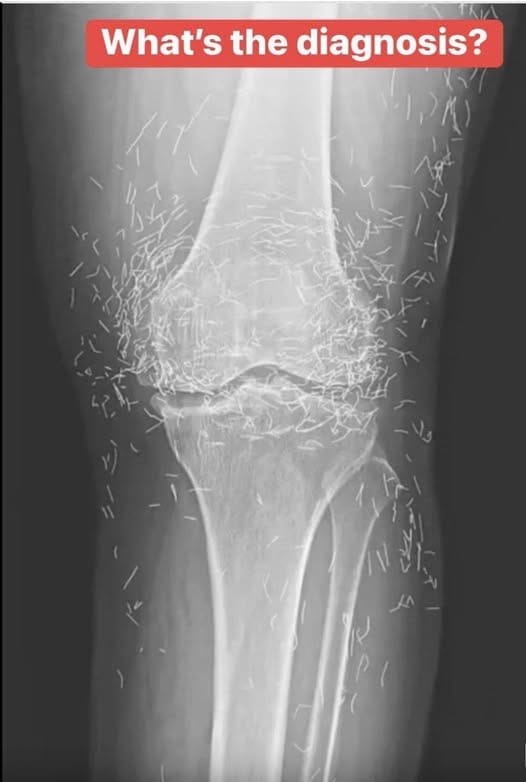

Years later, when doctors took X-rays to evaluate her knee condition, they weren’t prepared for what appeared on the images. Her knees were filled with dozens of bright, metallic flecks — tiny needles embedded deep within the joint area.

The findings were later documented in a case published by the New England Journal of Medicine.

Beyond inflammation, the needles created another problem: imaging complications. Metal objects can obscure parts of the anatomy on X-rays, making it harder for doctors to clearly assess joint damage or disease progression.

Even more concerning, the presence of metal inside the body can make certain scans dangerous. MRI machines rely on powerful magnetic fields, and embedded needles may shift during scanning, potentially damaging blood vessels or surrounding tissue. In short, future diagnostic options for this patient became limited.